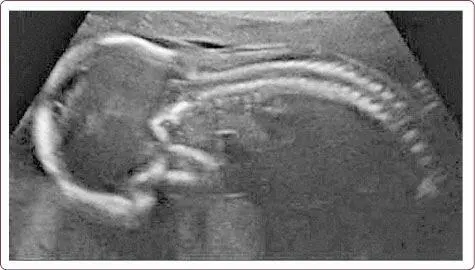

Ведь когда-то мы лежали в утробе матери, свернувшись в первичный изгиб зародыша (рис. 18). Вот так с возрастом мы снова возвращаемся к себе, к своим истокам, оправдывая поговорку: «Что стар, что млад» (рис. 19).

Рис. 18. Зародыш в утробе матери